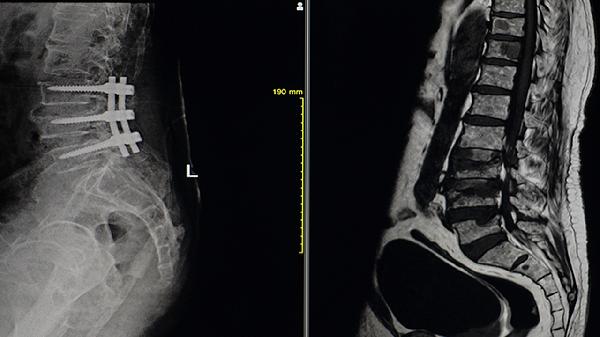

2、X线检查:

X线能显示特征性骨改变,包括长骨细长弯曲、多发性骨折愈合后的畸形骨痂、椎体压缩性骨折等。婴幼儿可见颅缝增宽和缝间骨,重症患者可能出现"爆米花"样骨骺改变。系列X线片可动态观察骨质变化。